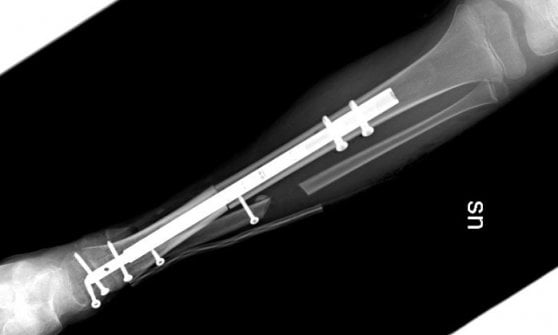

La bambina, affetta da una rara forma di sarcoma osseo, potrà tornare a camminare dopo che nei giorni scorsi, a seguito della diagnosi e della chemioterapia, era stata sottoposta all’intervento di asportazione del tumore e salvataggio della caviglia, con la ricostruzione grazie a un osso omoplastico da donatore e a un chiodo allungabile.

Una tecnica innovativa quella utilizzata dall’equipe del Regina Margherita di Torino: il perno inserito per stabilizzare l’impianto permetterà infatti nei prossimi anni la regolare crescita dell’arto permettendo l’allungamento al termine della maturazione scheletrica. La chirurgia è stata pianificata nei minimi dettagli dalle due équipe di medici ed ingegneri nelle settimane precedenti.